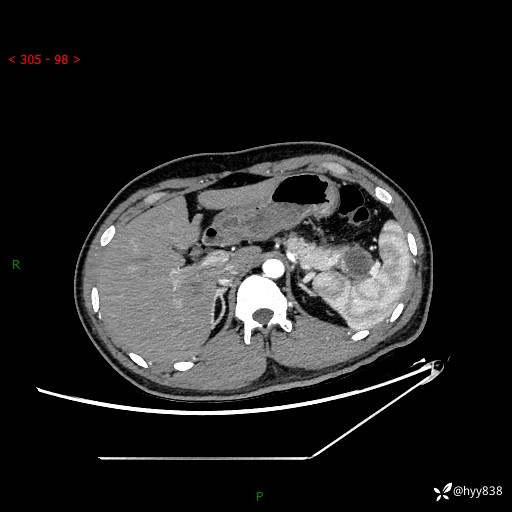

【患者信息】:31岁/男

【主诉】:间断性左下腹疼痛10天

【现病史及既往史】: 患者10余天前无明显诱因出现左下腹部疼痛,呈间断性,无恶心,呕吐,无黄疸,腹泻症状,于当地医院就诊,行腹部C提示:胰腺尾部占位。2型糖尿病。现患者为求手术治疗,门诊以“胰腺肿物”收入院。 患者起病来,一般情况可,大小便正常,体重体力未见明显减轻。

【检查】:胰腺CT平扫+增强